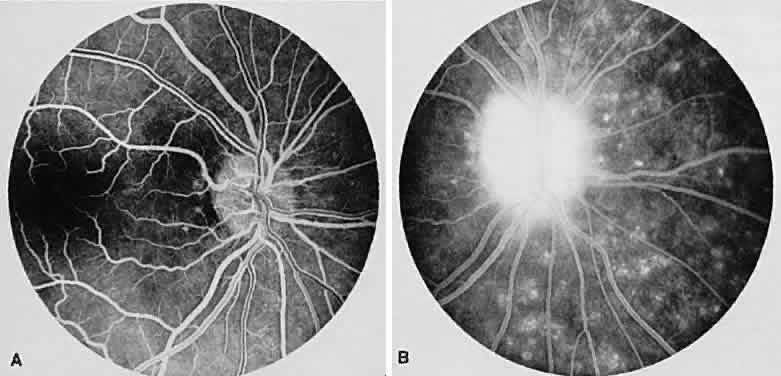

VOGT-KOYANAGI-HARADA SYNDROME

Vogt-Koyanagi-Harada syndrome, also known as uveomeningoencephalitis syndrome, is a systemic disease often found in young, darkly pigmented whites, blacks, native Indians, Hispanics, and Asians. It presents as an anterior and posterior uveitis with disc hyperemia, disc edema, and exudative retinal detachment (Figs. 2A and B and 3A). Systemic signs and symptoms include headache, hearing loss, poliosis, vitiligo, nuchal rigidity, seizures, and even coma. SRNV and disciform scars are late complications. The differential diagnosis should include AMPPPE and sympathetic ophthalmia.

Fig. 2. Vogt-Koyanagi-Harada syndrome. (A) Fundus photograph of the right eye and (B) the left eye showing bullous retinal detachments. (C) Fluorescein angiogram showing multiple hyperfluorescent leaks at the level of the retinal pigment epithelium. (D) Multiple coalescing leaks and fluorescein staining of the subretinal fluid. Large areas of hyperfluorescence involving the entire right posterior pole due to pooling of dye beneath the subretinal space.

Fig. 3. Vogt-Koyanagi-Harada syndrome. A. Fundus photograph of the left eye showing multifocal serous retinal detachment. B. Late fluorescein angiogram showing pooling of dye in the areas of serous detachment. C. Indocyanine angiography showing areas of blocked fluorescence corresponding to serous detachment. More areas of hypofluorescence are noted than those observed on fluorescein angiogram.

There is a characteristic fluorescein angiographic appearance in the early phase showing multiple discrete hyperfluorescent dots at the retinal pigment epithelial level that enlarge over time (see Fig. 2C and D). In the late phase, if there is a serous detachment, the fluorescein pools beneath the subretinal space (see Fig. 3B). The edematous disc hyperfluoresces in the late phase. Generally, the retinal vessels are unaffected.7,8 Retinochoroidal anastomoses also have been documented by fluorescein angiography.9

ICG angiography shows multiple hypofluorescent spots in the posterior pole (see Fig. 3C). These spots may coalesce and obscure the filling of large choroidal vessels. When serous retinal detachment develops, the marked hyperfluorescence observed on FA is not as prominently noted in ICG angiography, presumably because of the highly protein-bound nature of ICG. In fact, diffuse late hypofluorescence may be observed in patients with serous retinal detachment.10 Ill-defined areas of hyperfluorescence corresponding to diffuse choroidal staining may be seen in some cases in the late phases of the angiogram. The optic disc may stain with ICG in the acute phase but usually is minimal compared to that observed on FA.